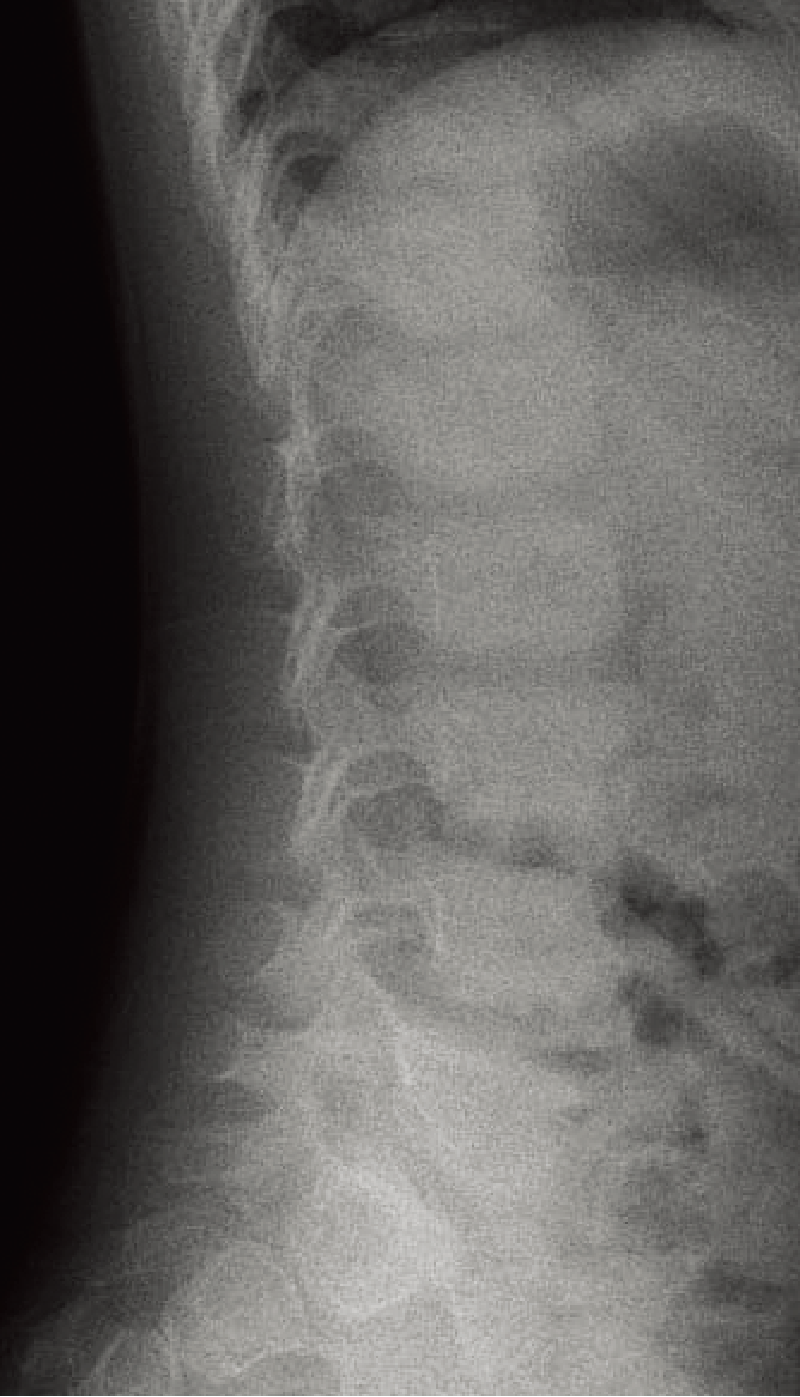

特徴的な画像所見:軽度から中等度の扁平椎、後弯、側弯、終板不整、Schmorl結節などの脊椎異常を認める(A)。

A. 腰椎側面像(5歳、男):軽度の扁平椎と終板不整。